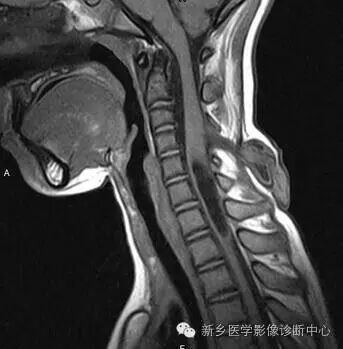

脊柱MRI提示椎管内占位及相应水平椎体后缘扇贝样压迹(白箭)